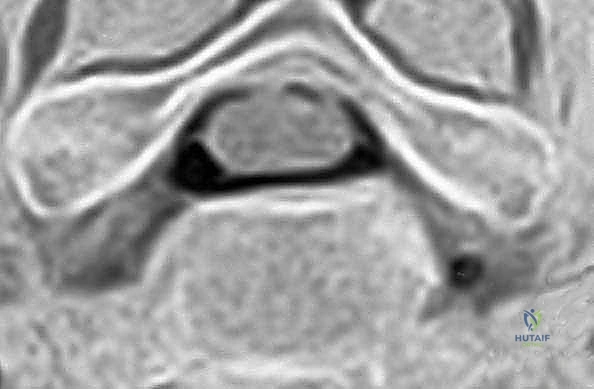

- التصوير بالرنين المغناطيسي (MRI): وهو الفحص الأهم لتحديد موقع الانزلاق الغضروفي بدقة ومدى انضغاط الأعصاب.

يحدث عندما تتمزق الحلقة الليفية الخارجية للقرص، مما يسمح للمادة الهلامية الداخلية (النواة اللبية) بالبروز والضغط المباشر على العصب الشوكي المجاور أو الحبل الشوكي نفسه.

الخطوة 5: تخفيف الضغط العصبي (Decompression)

هذه هي المرحلة الأهم والأكثر حساسية. يقوم الجراح بإزالة أي نتوءات عظمية (Osteophytes) أو أجزاء من الغضروف الممزق التي تضغط على الأعصاب الشوكية أو الحبل الشوكي، مما يعيد للقناة الشوكية اتساعها الطبيعي.